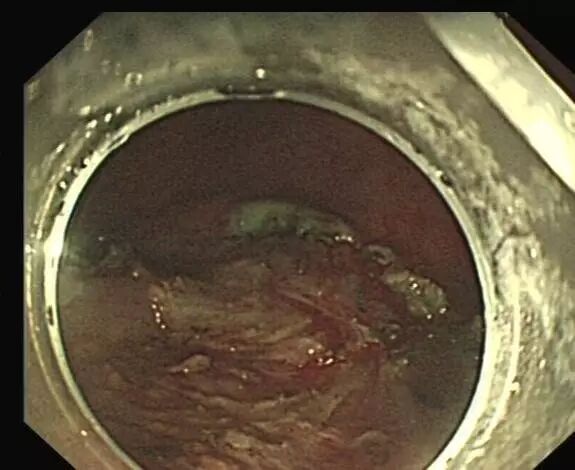

OTSC在消化道出血治疗中的应用

内镜夹怎么不掉CJP每周一帖--OTSC吻合夹系统在经内镜治疗消化道出血、穿孔及瘘中的应用_https://www.jmylbn.com_新闻资讯_第9张